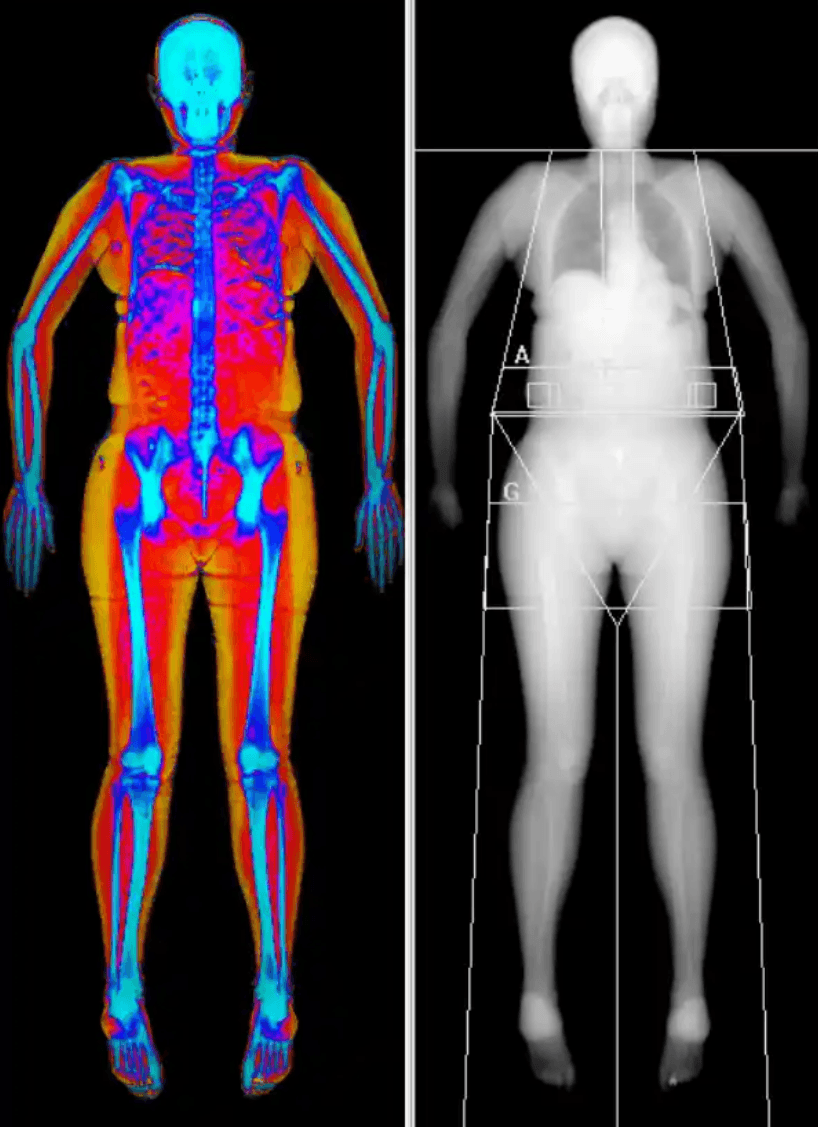

DEXA kroppssammansättning – analys av fett, muskelmassa och fettfördelning

DEXA är en av de mest precisa metoderna för att kartlägga kroppens sammansättning och ger detaljerade mätningar av fettmassa, muskelmassa och hur fettet är fördelat i kroppen. Undersökningen visar inte bara hur mycket kroppsfett du har, utan också var det är lokaliserat, inklusive skillnaden mellan subkutant fett och visceralt fett kring de inre organen.

Metoden räknas som ”golden standard” inom kroppssammansättningsanalys och används inom både medicin och idrott för att bedöma metabol hälsa, fysisk kapacitet och förändringar över tid.

Resultatet ger en detaljerad genomgång av din kroppssammansättning. Du får information om din totala fettprocent samt hur fettet är fördelat i kroppen. Fettfördelningen är särskilt viktig eftersom en hög andel bukfett är kopplad till ökad risk för hjärt-kärlsjukdom och metabola tillstånd. Analysen inkluderar även mätning av visceralt fett, det vill säga fett runt de inre organen. Detta redovisas som area, volym och massa och är en av de mest kliniskt relevanta markörerna för metabol risk.

Till skillnad från BMI, som endast baseras på vikt och längd, ger DEXA en detaljerad och medicinskt relevant bild av kroppens faktiska sammansättning. Kombinationen av fettfördelning, visceralt fett och muskelmassa ger en mer komplett förståelse av din hälsa.

Resultatet presenteras både visuellt och i siffror, vilket gör det möjligt att följa förändringar över tid och identifiera mönster som inte syns på vågen.

Vid undersökningen ligger du bekvämt på en brits medan en lågdosröntgen skannar kroppen. Genom att använda två olika energinivåer kan tekniken särskilja fettvävnad, muskelmassa och ben med mycket hög precision. Undersökningen är helt smärtfri och tar cirka 10–20 minuter. Stråldosen är mycket låg och motsvarar ungefär den naturliga bakgrundsstrålningen du exponeras för under en dag.